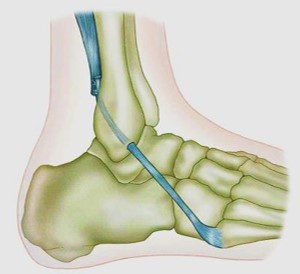

Тенодез Эванса (Evans D.L.,1953) в техническом отношении является наиболее простым вариантом вмешательства (рис.7.4). Однако этот тенодез в биомеханическом плане не связан с реконструкцией ни передней таранно-малоберцовой, ни пяточно-малоберцовой связок — формируемая новая связка здесь будет располагаться примерно между ними. Ряд авторов отмечают, что ближайшие результаты этой операции и ее модификаций, довольно неплохие, тогда как отдаленные результаты отличаются вариабельностью. У многих пациентов с удовлетворительными ближайшими результатами через несколько лет после операции наступает ухудшение. В одном из исследований показано, что удовлетворительный результат при среднем периоде наблюдения 14 лет сохранялся менее, чем у 50% пациентов (Karlsson et al. 1988).

Рис. 7.4. Тенодез Эванса